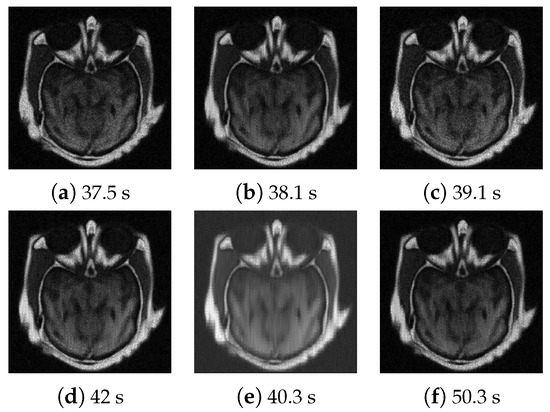

4.3. Numerical Experimental Results and Analysis

| Test Images | Peak | Noisy | PSNR | |||

|---|---|---|---|---|---|---|

| CT/MRI | 55 | 31.17/24.39 | 31.70/26.79 | 1.83 | 0.50 | 0.56 |

| 155 | 35.70/28.85 | 36.06/28.95 | 2.55 | 0.59 | 0.48 | |

| MR-T1/MR-T2 | 55 | 27.98/23.90 | 29.91/26.15 | 2.61 | 0.40 | 0.53 |

| 155 | 32.41/28.40 | 32.86/28.29 | 3.16 | 0.47 | 0.41 |